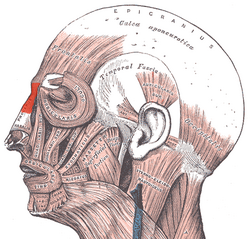

- Nasal muscles – The movements of the human nose are controlled by groups of facial and neck muscles that are set deep to the skin; they are in four (4) functional groups that are interconnected by the nasal superficial aponeurosis—the superficial musculoaponeurotic system (SMAS)—which is a sheet of dense, fibrous, collagenous connective tissue that covers, invests, and forms the terminations of the muscles.

- the elevator muscle group includes the procerus muscle and the levator labii superioris alaeque nasi muscle.

- the depressor muscle group includes the alar nasalis muscle and the depressor septi nasi muscle.

- the compressor muscle group includes the transverse nasalis muscle.

- the dilator muscle group includes the dilator naris muscle that expands the nostrils; it is in two parts: (i) the dilator nasi anterior muscle, and (ii) the dilator nasi posterior muscle.